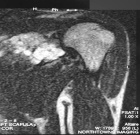

Case 6

27 year old male presents with pain in his left shoulder for about one year

Zoom image: Radiological image Radiological image.

Zoom image: Cell stain Cell stain.